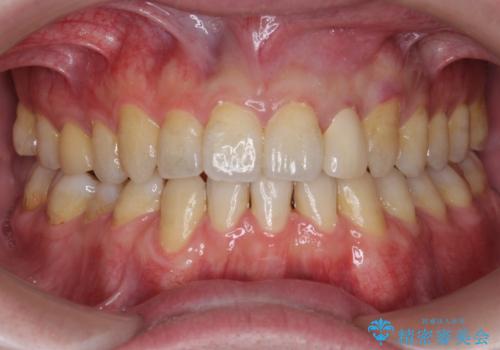

- 上下の前歯が気になり来院。

左上2が矮小歯で小さく、また、左の奥歯が反対咬合になっていました。

左上2番はセラミッククラウンで反対側と同じ大きさにしました。